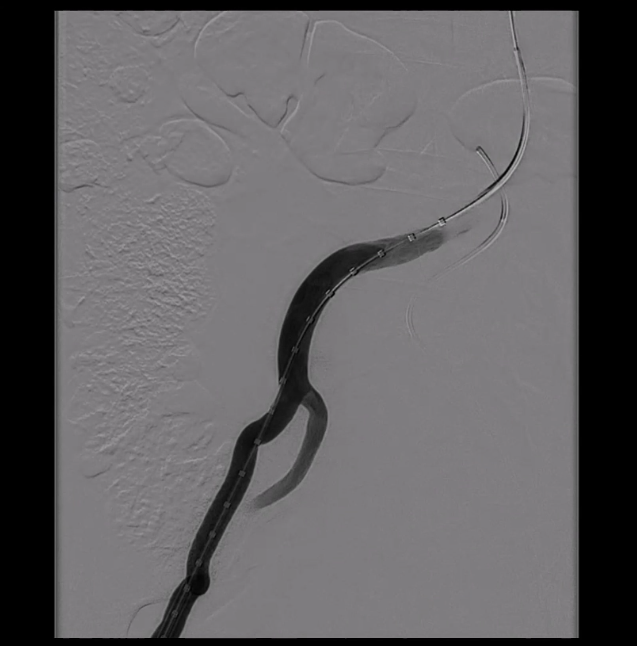

从右侧股动脉入路,使用超滑导丝进入真腔,置入金标猪尾导管造影,再次造影明确夹层真腔位置、形态,可见腹主动脉及降主动脉真腔处多处严重狭窄受压,假腔呈瘤样扩张并累及左侧锁骨下动脉。

通过左侧股动脉入路置入猪尾导管,并在超硬导丝引导下置换24F大鞘,缓慢送入防缠绕导管至主动脉弓部。

3. 关键分支处理环节,分支导丝超选与抓捕建立分支导丝通路

使用4F 导管和抓捕系统,分别超选弓上三分支(无名动脉、左颈总、左锁骨下动脉)

14系统导丝经防缠绕导管引出至右侧股动脉输送鞘外,建立分支导丝通路。